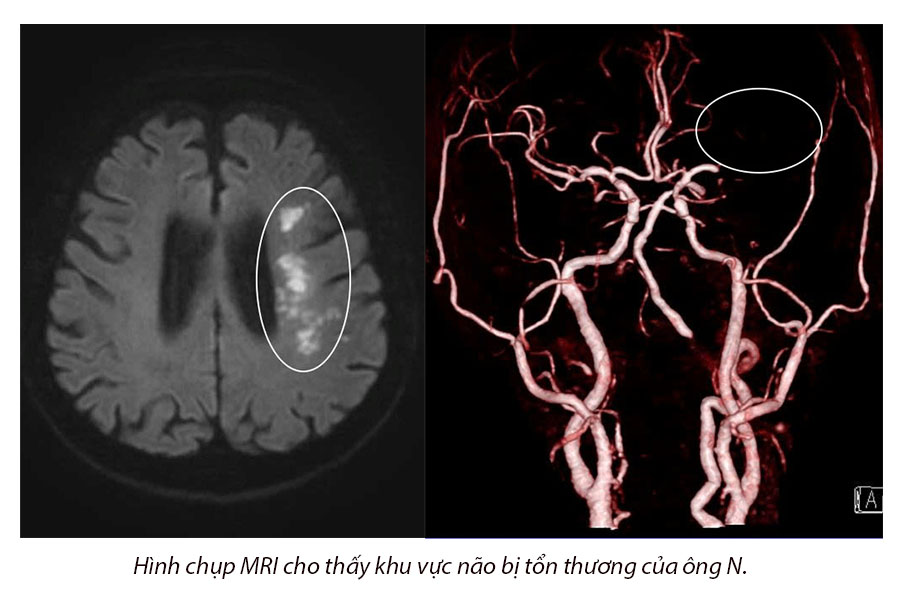

Bệnh nhân nhập viện cấp cứu trong tình trạng liệt nửa người, nói đớ, có tiền sử huyết áp cao. Qua các xét nghiệm, chụp kiểm tra cận lâm sàng cần thiết, bác sĩ chẩn đoán ông bị tắc động mạch não giữa trái do rung nhĩ cơn. Là bác sĩ theo dõi bệnh cho ông N., Ths.BS Diệp Tiến Đạt – Khoa Thần kinh – Đột quỵ cho biết:

“Bệnh nhân khá lớn tuổi bị đột quỵ nên tiên lượng khá nặng. Đối với bệnh nhân lớn tuổi bị đột quỵ nguyên nhân thường là do hẹp mạch máu não. Tuy nhiên, bệnh nhân được bác sĩ chỉ định khảo sát thêm holter điện tim 24h. Kết quả phát hiện bệnh nhân có tình trạng rung nhĩ cơn. Các cục huyết khối được hình thành từ tim chảy lên não gây tắc động mạch não giữa trái dẫn đến đột quỵ. Từ đó, bác sĩ mới tìm ra nguyên nhân và điều trị đúng cho bệnh nhân. Trường hợp nếu không tầm soát kỹ để tìm ra nguyên nhân gây đột quỵ cho ông cụ thì có thể bỏ sót nguyên nhân do rung nhĩ cơn. Từ đó, bệnh nhân không được can thiệp điều trị triệt để sẽ dễ bị đột quỵ tái phát”.